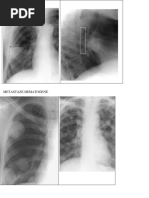

Rx pulmonar: cord marit de volum, orizontalizat, hiluri cu arie de proiectie marite, probabil

vascular, teritorii bronsiectatice bazal bilateral, desen peribronhovascular intarit bilateral, SCD

opacifiat bilateral

Radiografie toracica: multiple opacitati fibroase nodulare si lineare apico-caudal bilateral;

apicalizarea hilurilor pulmonare; opacitate triunghiulara cu caracter sechelar paratraheal drept

Gazometrie: hopoxemie severa cu hipercapnie moderata ce au necesitat instituirea

Rx pulmonara: LSS distrus TB, sechele fibroase post TB apical bilateral, teritorii bronsiectatice

paracardiac bilateral, cord marit de volum, opacitate cu caracter pneumonic paracardiac drept,

mediastin largit de volum.